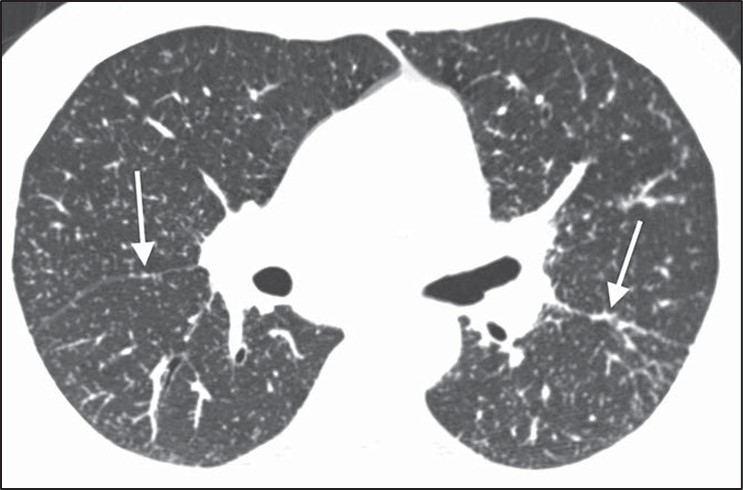

Although many centrilobular nodules may be present in lymphatic diseases, nodules should also be seen in the peribronchovascular or sub- pleural interstitium. This is in distinction to the centrilobular pattern in which only centrilobular nodules are present and no subpleural nodules should be seen. Lastly, diseases typically associated with a perilymphatic distribution of nodules (such as sarcoidosis) may occasionally show a fairly homogeneous involvement of the lung, mimicking a random distribution [27] (Fig. 11).

Fig. 11—Axial high-resolution CT scan shows perilymphatic distribution mimicking random nodules. Innumerable tiny nodules are present. Although pattern resembles random distribution, heterogeneous distribution in lung shows proportionally more nodules along fissures (arrows) than would be expected for random distribution.

A greater number of nodules in the subpleural or peribronchovascular interstitium may be the only clue that the distribution is perilymphatic.